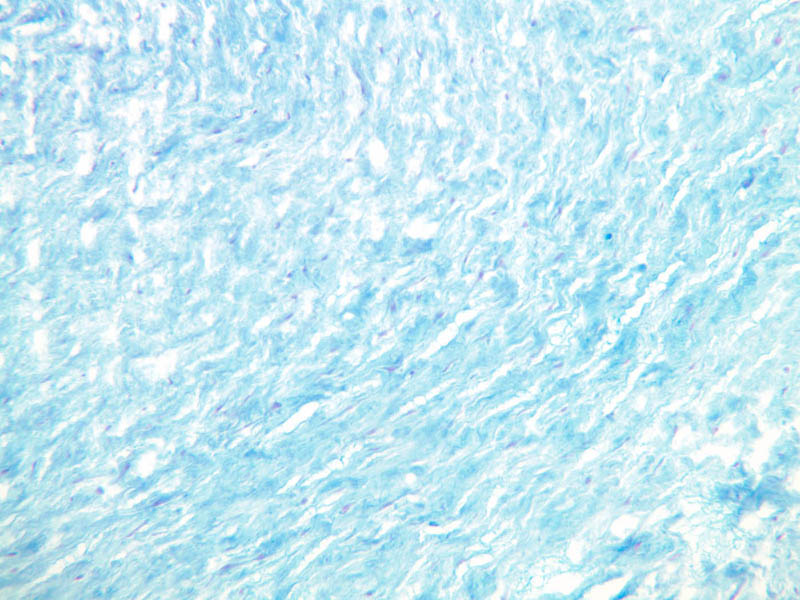

a95_mucous_ct_umbilical_cord_10x.jpgjpg a95_mucous_ct_umbilical_cord_10x.jpg manage 125 K 31 May 2007 - 22:40 AshleyLPistorio 2 - A95, Umbilical Cord, 10x (Alcian Blue)

a95_mucous_ct_umbilical_cord_20x.jpgjpg a95_mucous_ct_umbilical_cord_20x.jpg manage 104 K 31 May 2007 - 22:40 AshleyLPistorio 3 - A95, Umbilical Cord, 20x (Alcian Blue)

a95_mucous_ct_umbilical_cord_2x.jpgjpg a95_mucous_ct_umbilical_cord_2x.jpg manage 109 K 31 May 2007 - 22:40 AshleyLPistorio 1 - A95, Umbilical Cord, 2.5x (Alcian Blue)